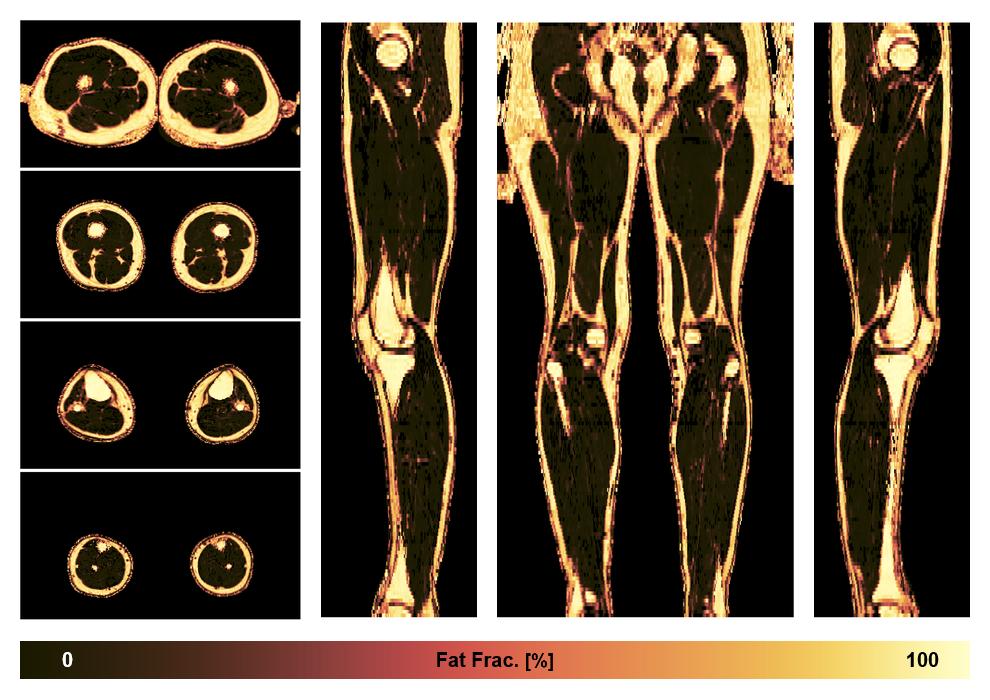

• Fat fraction

The fat fraction of the lower extremity obtained from the dixon reconstruction for muscle water fat quantification.